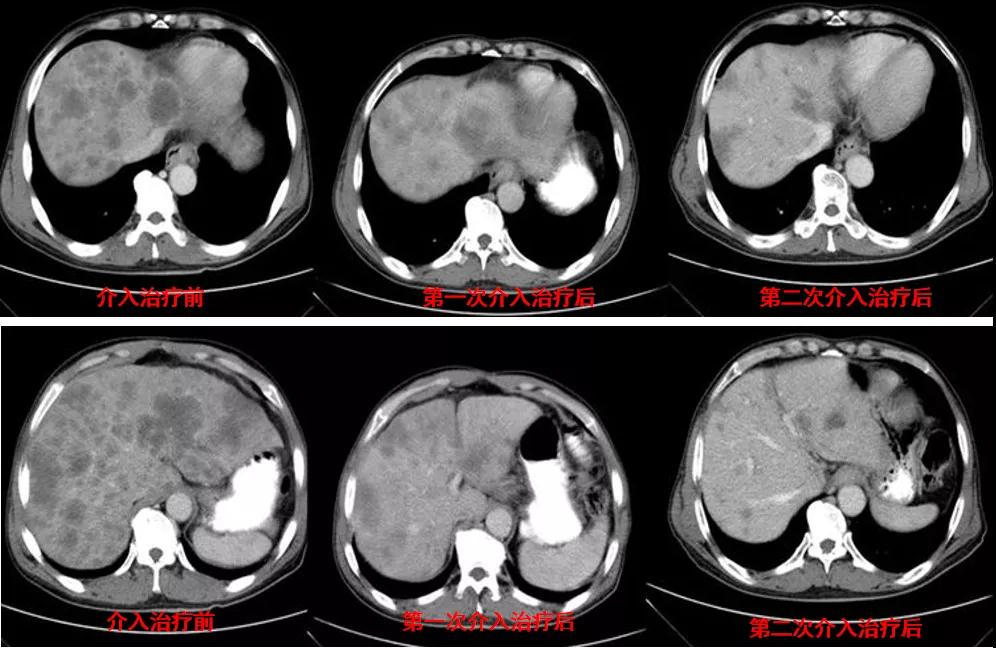

诊治经过:2021年5月16日患者行第三次经皮动脉化疗灌注栓塞术(铂类+氟尿嘧啶)治疗,并继续联合吡咯替尼治疗。结果见图4。

图4

总结:本例患者为胃癌IV期,伴肝转移及淋巴结转移,经介入联合吡咯替尼治疗后,肝转移灶显著缩小。治疗前肿瘤标志为:癌胚抗原3574.3ng/ml、CA12-5 650U/ml、CA19-9 1212U/ml、CA15-3 333U/ml;治疗后肿瘤标志为:癌胚抗原7.6ng/ml、CA12-5 12.8U/ml、CA19-9 17.4U/ml、CA15-3 6.7U/ml。治疗后,肿瘤标志物显著降低,且腹部CT结果显示该患者肝转移病灶较治疗前明显减少。患者目前带瘤总生存达10个月,病情稳定。